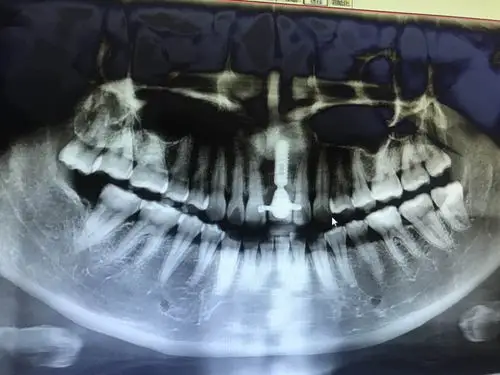

这个牙槽骨吸收的严重吗?

牙槽骨吸收

牙槽骨吸收是什么意思还能治疗吗

牙槽骨重度吸收图片

牙槽骨吸收(不是牙周炎造成的)

有没有牙科医生帮我看看我的种植牙 牙槽骨吸收情况 植体有问题吗5555

检查:结合cbct,36牙槽骨吸收严重,无保留价值.